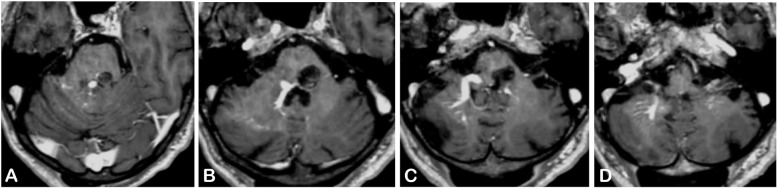

Fig. 3.

Postoperative MRI of the brain in post-contrast T1-weighted sequence. We performed (d) a suboccipital telovelar approach to gain access to the rhomboid fossa. Then we used (c) the infrafacial triangle as an entry point to the pons to perform microsurgical excision of (a) the BCM and (b,c) the pontine hematoma. a,b,c,d The DVA was left intact